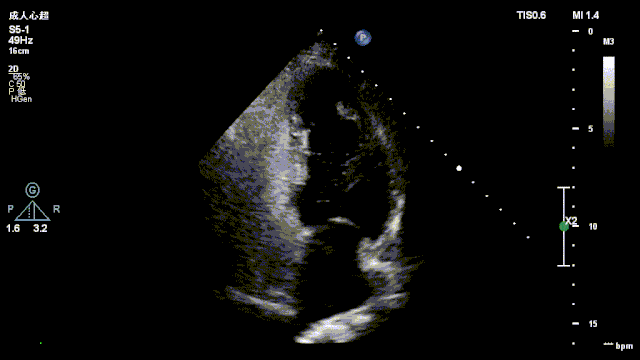

一例卵圆孔未闭患者声学造影图像

图片尺寸640x360